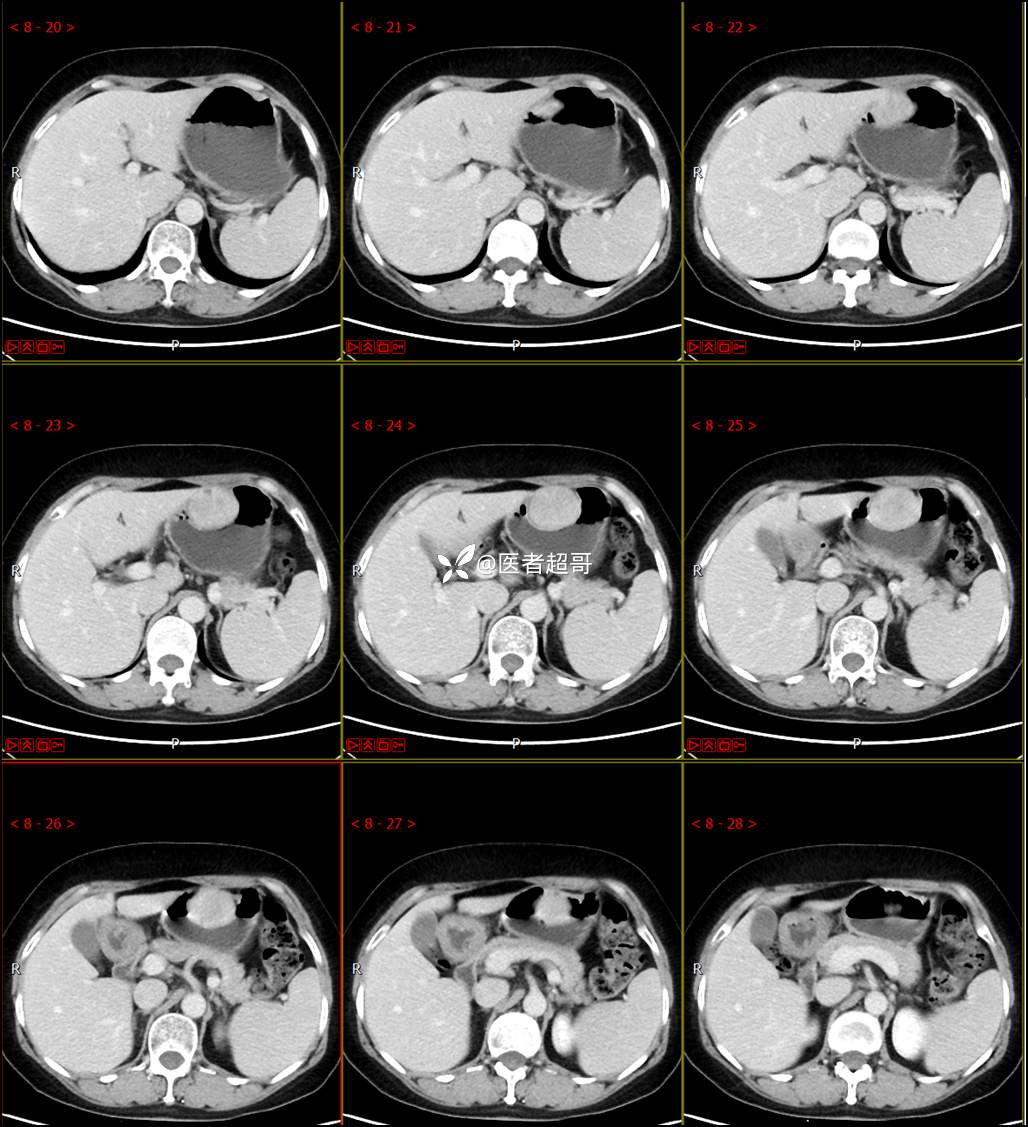

【影诊笔记759】胃体巨大隆起,间质瘤?神经鞘瘤?平滑肌瘤?请鉴别诊断!有结果!

患者半月前无明显原因及诱因出现上腹部疼痛不适,以夜间腹痛为主,无放射性疼痛,间断嗳气,无反酸烧心,无腹泻黑便,于我院门诊行胃镜显示:胃体前壁巨大隆起型病变。